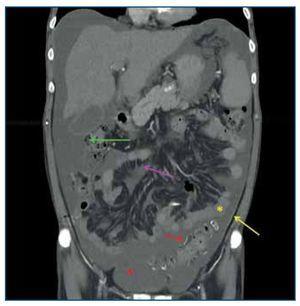

Figura 3.Tomografía computarizada abdominopélvica tras administración de contraste intravenoso, reconstrucción coronal. Se observa engrosamiento y realce aumentado del peritoneo parietal (flecha amarilla) y del peritoneo visceral (flecha verde), calcificaciones «en sábana» del peritoneo visceral, engrosamiento del mesenterio de las asas intestinales (flecha rosa) por el desarrollo de membranas fibróticas que retraen las asas de intestino delgado adyacentes, asas de intestino delgado de diámetro intraluminal disminuido (asterisco amarillo) y ascitis loculada perihepática, periesplénica, en ambas gotieras paracólicas y en pelvis (asterisco rojo).